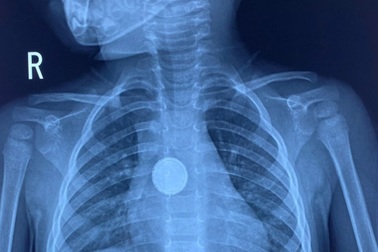

Gắp thành công viên "pin cúc" từ thực quản bé gái 3 tuổiCác bác sỹ Khoa Tai - Mũi - Họng của Bệnh viện Đa khoa tỉnh Lào Cai vừa cấp cứu thành công trường hợp bé gái 3 tuổi không may nuốt viên pin điện tử vào trong thực quản.

Bé gái 16 tháng tuổi cấp cứu vì nuốt viên pin trong đồ chơiChiều 28/2, Bệnh viện Đa khoa Trung ương Quảng Nam (đóng tại huyện Núi Thành) cho biết, vừa nội soi gắp thành công một viên pin kích thước lớn trong dạ dày bé gái mới 16 tháng tuổi.